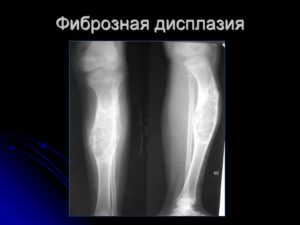

- Рентгенологическая картина фиброзной дисплазии разнообразна.

- Патологические участки могут быть то более плотными, то более прозрачными по сравнению с окружающей костью, иногда имеют вид «матового стекла».

- Одни очаги четко отграничены зоной склероза, контуры других расплывчатые, что особенно характерно для костей черепа.

- Нередко выявляются узуры в кортикальном слое, а при наличии перелома — отчетливая периостальная реакция.

- затемнение по типу матового стекла: 56% [1]

- очаг однородный склеротический: 23%

- очаг кистозный: 21%

- очаг с четко определенными границами

- расширение костей с интактными вышележащими костями

Фиброзная дисплазия может поразить любую кость. И диффузные, и очаговые поражения располагаются в диафизах и метафизах, чаще всего в длинных трубчатых костях рук и ног. Наиболее часто этой болезни подвергаются большеберцовая, бедренная, лучевая и плечевая кости, также нередко страдают ребра.